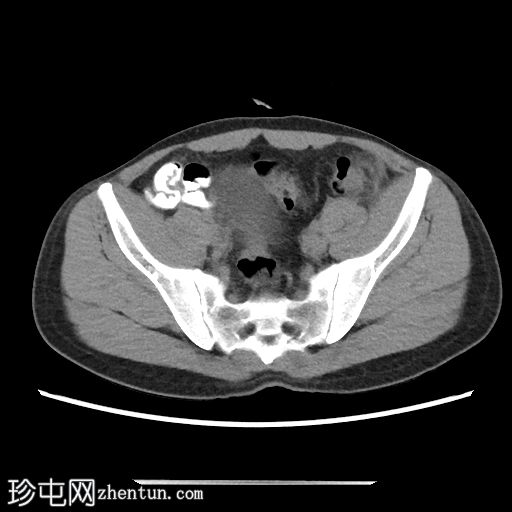

2.png

冠状位

平扫

乙状结肠-降结肠交界处前缘可见一卵圆形脂肪密度病灶,大小约20 x 7 mm(TR x AP)。病灶周围可见高密度环及脂肪条索影,符合大网膜垂炎的影像学表现。

邻近肠壁可见轻度反应性增厚。

未见腹腔积液或肠系膜淋巴结肿大。